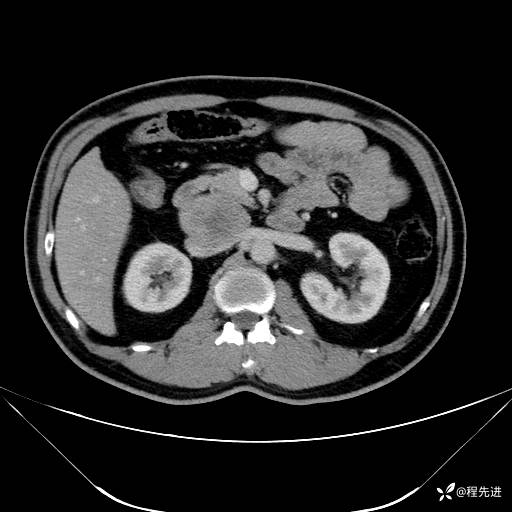

【腹盆】特别精彩病例|发现腹膜后肿物1月余

主诉:发现腹膜后肿物1月余

现病史:患者1月余前查体,行超声检查提示:后腹膜囊实性肿块;慢性胆囊炎伴胆囊内结石;无腹痛腹胀,不伴腹泻发热等;偶感腰背部酸痛。

CT平扫+增强: